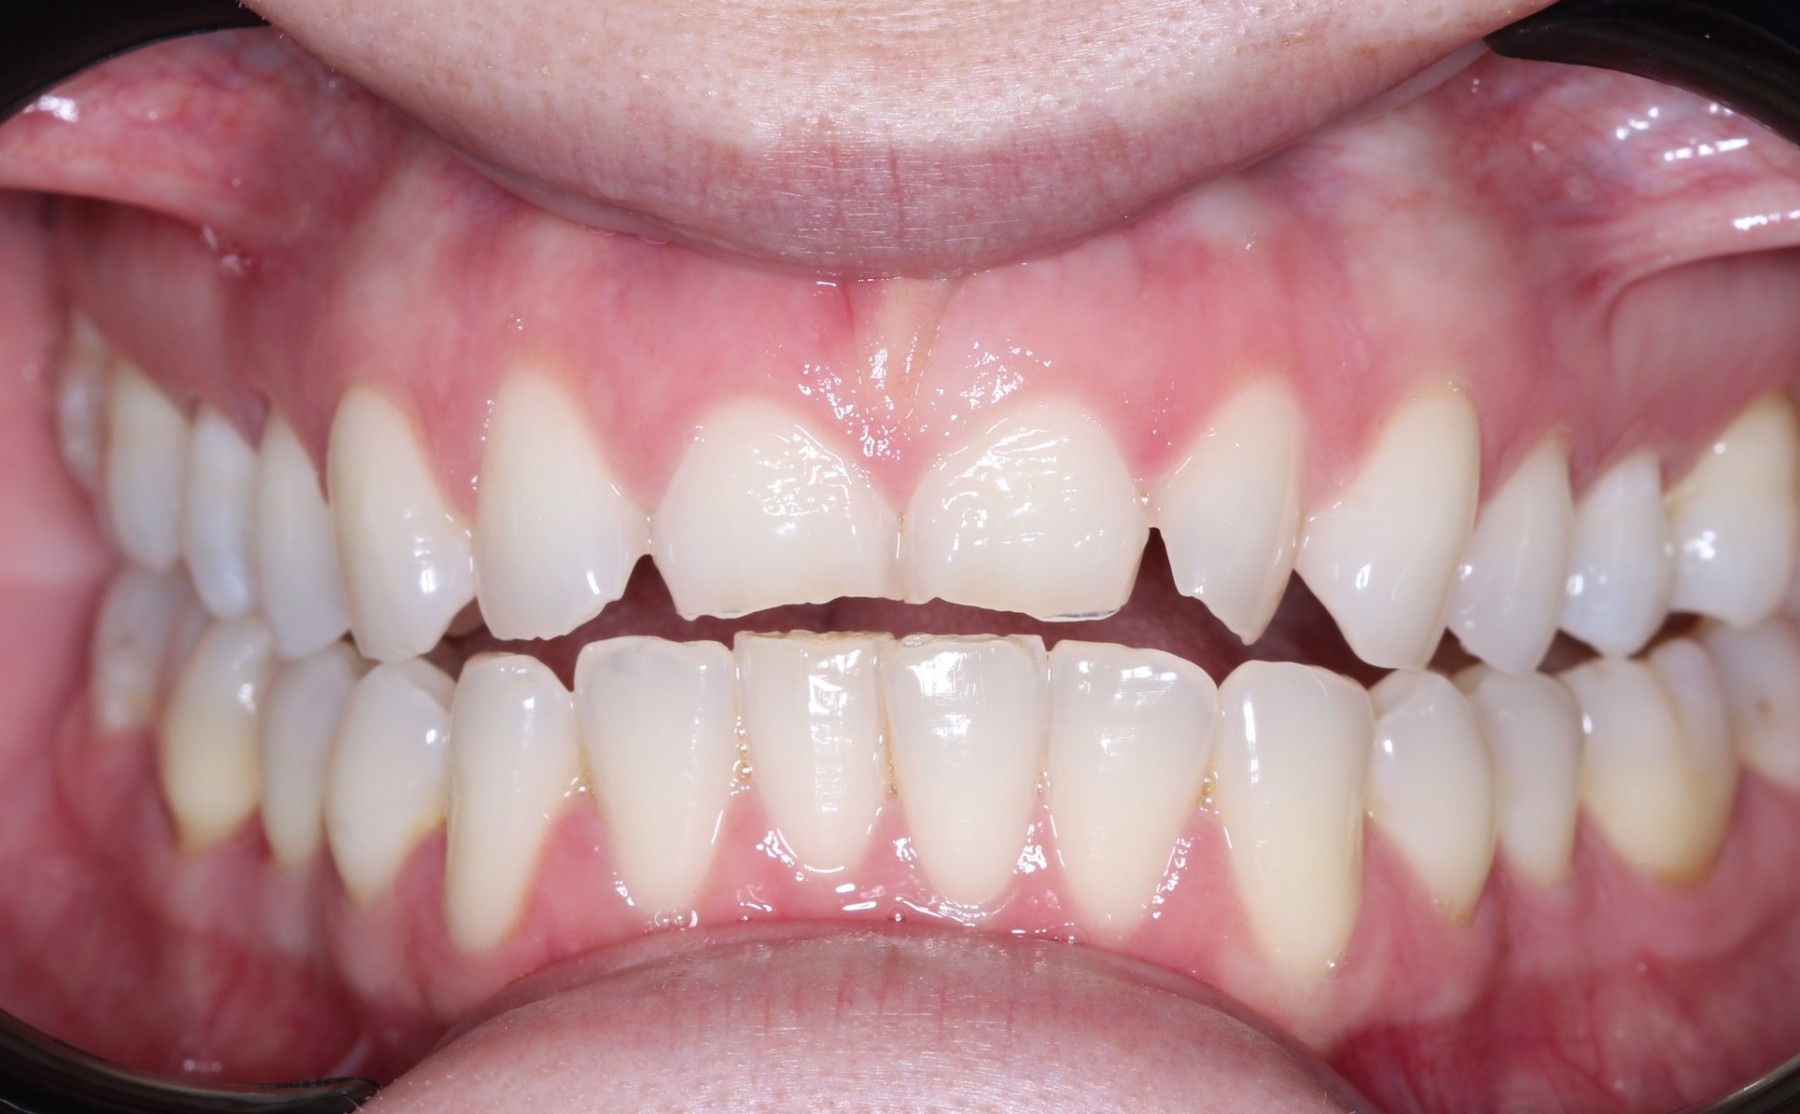

Paciente femenina, 19 años, con agenesia dental (ausencia de piezas de nacimiento), se realiza colocación de 2 implantes en piezas laterales, confección de provisionales y se esperan 4 meses para la colocación de piezas permanentes sobre implantes.